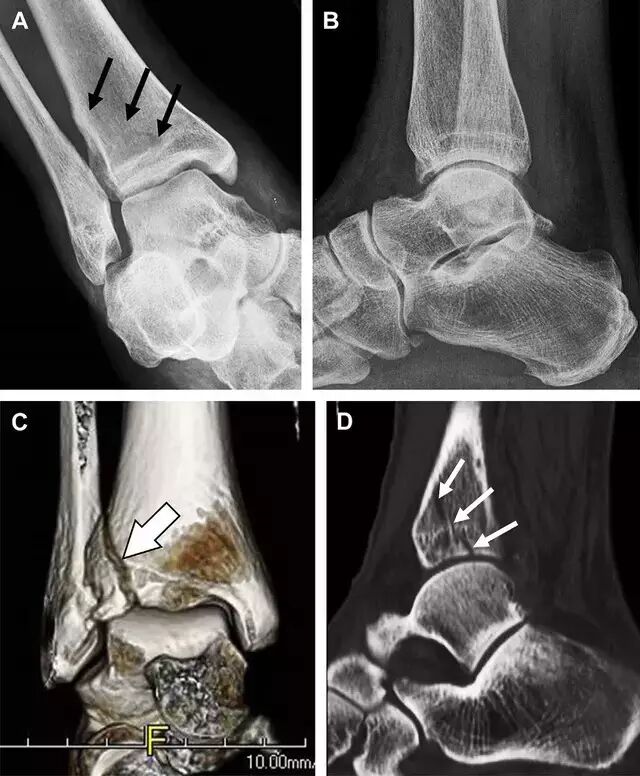

急诊科医生常遇到的一个问题是:踝关节疼痛。对于这类患者,想要分辨是否存在骨折,X 线检查是主要手段。然而,由于各种原因,有些踝部骨折非常容易漏诊。

首先,来看踝关节骨折的高危区(图 1)。

图 1 踝部探查模板。阅片时,需对踝关节的前后位片(A)、内旋转位片(B)侧位片(C)仔细阅读,逐一详细排查。上图中的骨折:1. 内踝骨折,2. 外踝骨折,3. 胫骨结节骨折,4. 胫骨后踝骨折,5. 距骨骨软骨骨折,6. 距骨外侧突骨折,7. 距骨后突骨折,8. 距骨舟骨关节背侧骨折,9. 跟骨前突骨折,10. 跟骨骨折嵌插入趾短伸肌,11. 第五跖骨底骨折

涉及到三角韧带和外侧副韧带(LCL)的复杂性骨折常常不难发现,尤其是存在表面软组织肿胀时。然而,后胫腓韧带牵拉引起的胫骨后踝骨折则很难发现。这些骨折大小不一(图 2),却很重要,因为他们常与胫骨远端螺旋骨折有关,或者是三踝骨折的一部分。

图 2 胫骨后踝骨折。A 侧位片示来源于胫骨后踝的一个小骨折碎片(箭头),因踝部扭伤导致;B 另一位跖屈损伤的患者,侧位片示一个大骨折块(箭头)

Tillaux 骨折,是足外旋外展时,胫腓前韧带牵拉引起的一种胫骨结节撕脱性骨折。斜位片上可见典型表现(图 3)。

图 3 摔倒后胫骨结节骨折。A 正位片示一细小斜型骨折线(箭头);B 侧位片示正常;C 冠状位 CT 三维成像更清晰地显示了骨折线和骨折块大小(空箭头);D 矢状位 CT 多维重建图像示骨折位置(箭头)

距骨外侧突骨折常因踝外翻背屈时,跟骨上外侧面撞击距骨外侧突下缘导致,或偶尔由踝内翻引起,被称为「滑雪板者骨折」。这种骨折只能在踝关节正位片上发现,而且外踝远端表面软组织肿胀往往是一个重要线索(图 4)。

图 4 距骨外侧突骨折。A 正位片示内翻损伤所致的距骨外侧突撕脱性骨折(箭头);B 另一位患者,踝外翻损伤导致典型的「滑雪板者骨折」,X 片上可见一较大的三角形骨折块(方框);C 第二位患者的 MRI 矢状位 T1 加权像示横行骨折(箭头)

距骨后突有内侧结节和外侧结节,距骨后突内侧结节撕脱性骨折常发生在背屈内旋的暴力作用下。严重跖屈时,胫骨后缘和跟骨挤压距骨后突外侧结节呈楔形,易发生粉碎性骨折。这些骨折细微且需与三角骨鉴别。侧位片观察距骨后突骨折最佳,常规拍片很难发现,当高度怀疑这种骨折又没法做 CT 时,建议加做多个角度的外旋斜位片(图 5)。

图 5 距骨后突骨折。侧位片(A)和 MRI 矢状位 T1 加权像(B)均示后外侧突的简单骨折(箭头),再次阅片时才发现 X 线片上的骨折;侧位片(C)和 CT 横断面图像示后内侧突的粉碎型骨折(箭头)

呈 Y 形的分歧韧带附着于跟骨前突上,是维持踝关节跖屈和背屈稳定性的重要结构。跟骨前突骨折常发生于足跖屈内旋、分歧韧带被牵拉时,或者足背屈外旋、骰骨和距骨挤压前突时。而这些骨折在初次 X 线检查时常常被漏诊掉。踝部侧位片诊断这些骨折最佳,准确诊断的关键点在于,必须仔细查看是否存在骨皮质中断(图 6)。如果侧位片可疑,建议加做斜位片协助诊断。

图 6 跟骨前突骨折。A 侧位片示跟骨前突骨折(箭头),与舟骨的重叠使骨折显示模糊;B 另一位患者的侧位片示内翻损伤所致的骨折(箭头),这种损伤机制引起小块的骨折

另一种重要的跟骨撕脱性骨折,于足内翻时发生在趾短伸肌的起点处。观察来自跟骨背外侧的、不同大小的骨折块,前后位 X 片最适合不过了(图 7)。

图 7 溜冰受伤的患者,趾短伸肌跟骨撕脱性骨折。正位片示 2 个骨折块(箭头)来源于跟骨前外侧、趾短伸肌的起点处。踝关节外侧远端是否存在软组织水肿是一个重点观察点